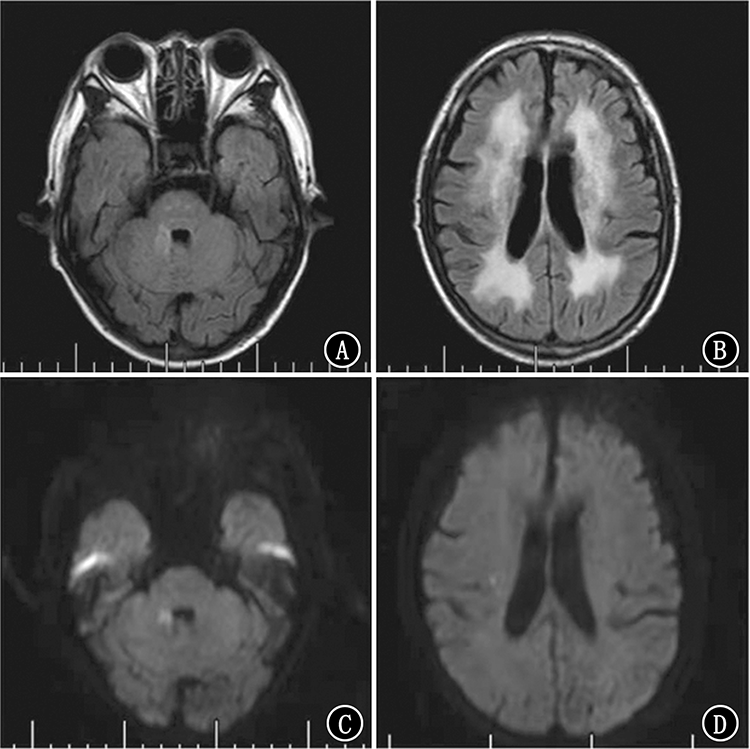

王丽, 刘志华, 杨伟洪, 蒋凤莲, 李全泳, 宋浩杰, 鞠文东. ROS1突变肺腺鳞癌合并脑梗死为主要表现的Trousseau综合征1例[J]. 国际肿瘤学杂志, 2024, 51(6): 382-384. |